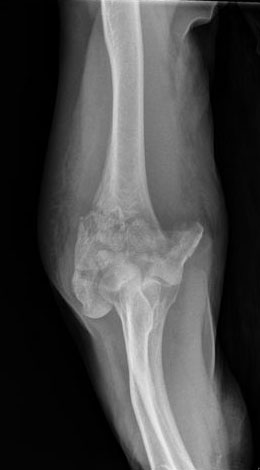

Fractura compleja de húmero.

Fractura de húmero, intensa desviación de fragmentos